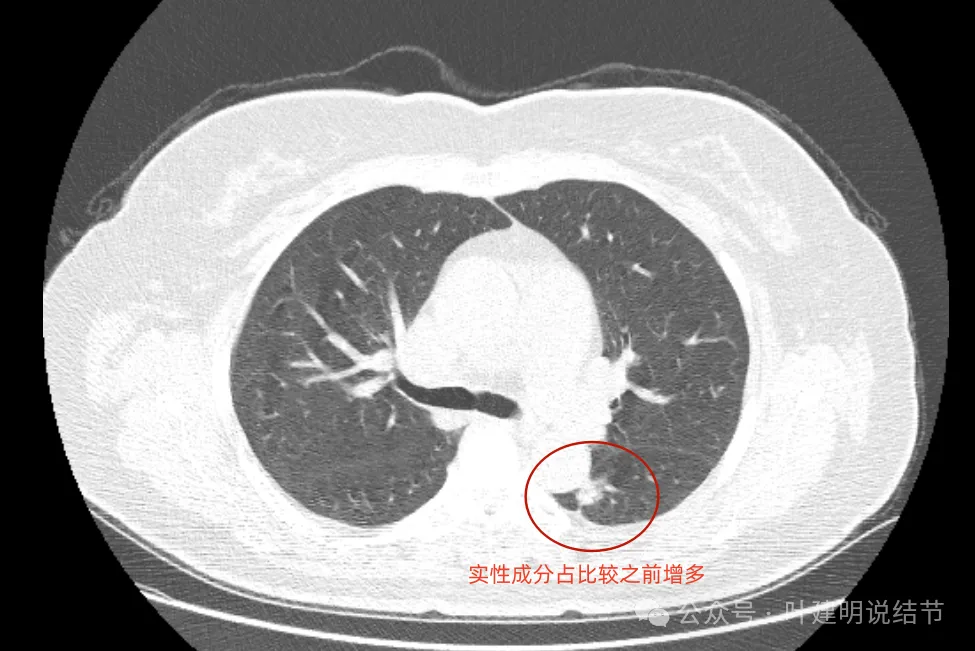

最后看2024年复查的影像:

病灶出现,密度不纯,毛刺细长。

轮廓稍显模糊,密度不均,毛刺偏长。

实性成分似乎较前增多,胸膜略有牵拉。

实性成分占比增加,邻近结构受压,边缘毛刺出现。

现在较2年前有进展,显示了更多的恶性影像特征,整体密度也增加,膨胀性也明显起来,并对邻近结构有压迫,表面不平毛糙。持续存在的实性为主的结节随访进展,并显示出更多恶性特征,那就得高度怀疑恶性,而且不宜再随访了。